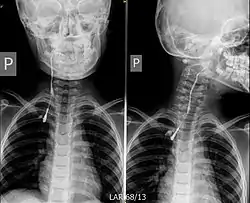

![]() تصوير الناسور لكيسة الفلح الخيشومي ثنائية الجانب. تصوير الناسور لكيسة الفلح الخيشومي ثنائية الجانب. | |